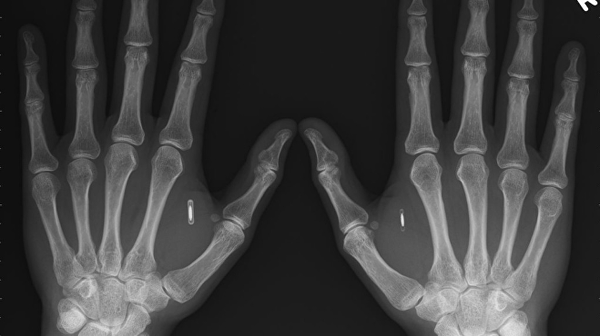

NFC-чипы вживляют в мягкие ткани между указательным и большим пальцем при помощи специального шприца. Процедура полностью безопасна, заверила сертифицированный специалист по установке чипов Сандра Мюйр. По ее словам, манипуляция напоминает взятие крови на анализ.